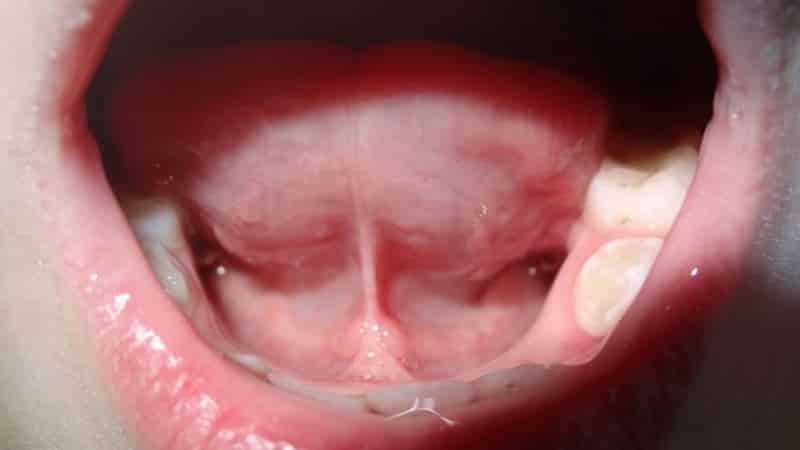

Воспаление уздечки под языком, или френит, может проявляться различными симптомами, которые могут варьироваться по степени выраженности. Основные признаки воспалительного процесса включают:

- Отек: Воспаление может приводить к отеку уздечки, что делает ее более заметной и может затруднять речь и глотание.

- Затрудненное движение языка: Из-за боли и отека может наблюдаться ограничение подвижности языка, что затрудняет выполнение обычных функций, таких как речь и еда.

- Визуальный осмотр: Специалист осматривает уздечку и окружающие ткани на наличие покраснения, отека, язв или других изменений.